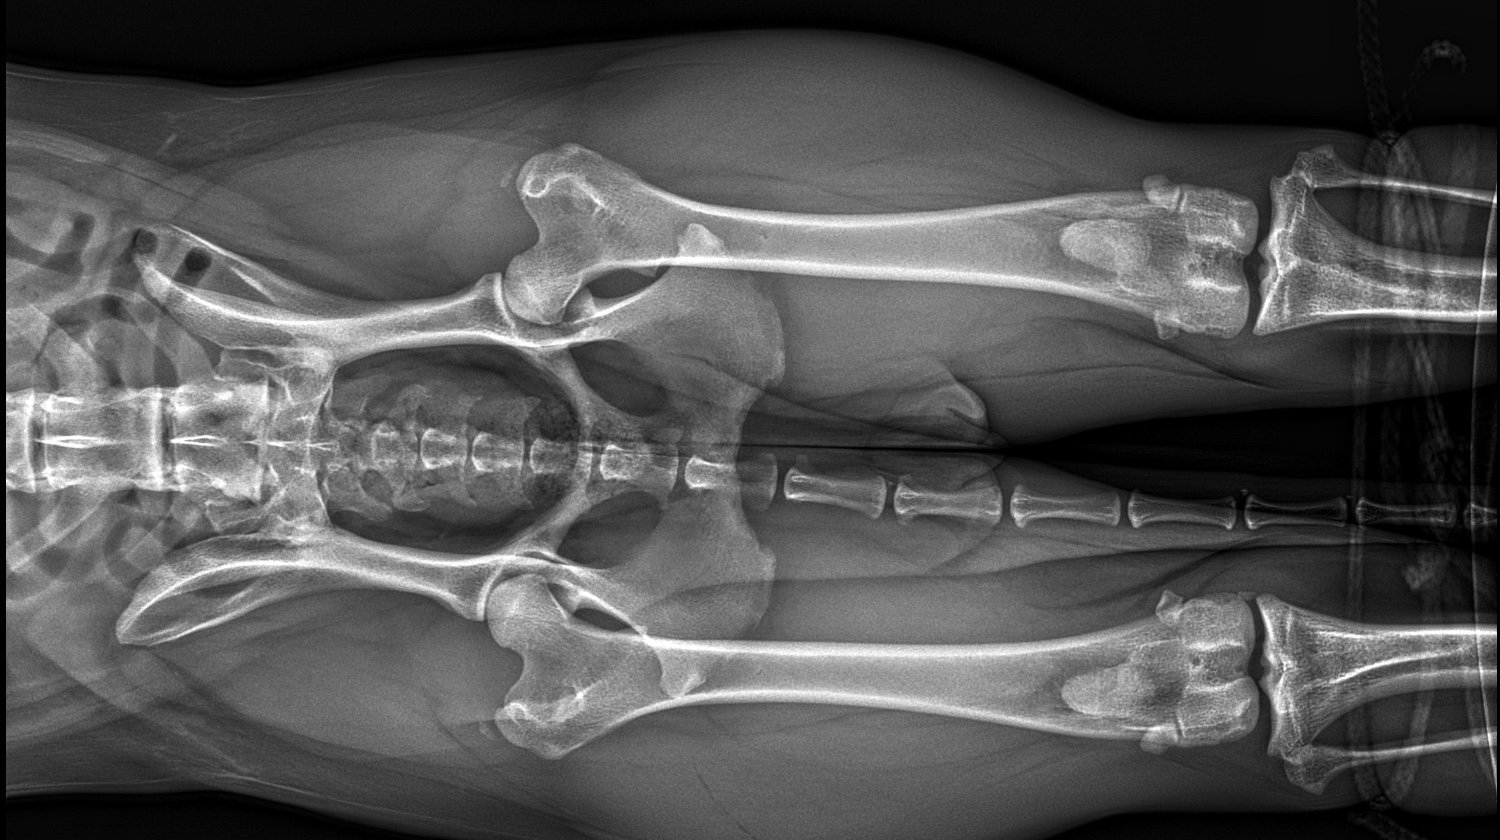

-zmiany w typie spondylozy w kręgosłupie piersiowym Th9-Th13

-sklerotyzacja blaszki granicznej kręgu S1

-brak jednego członu kości krzyżowej

-obustronna mineralizacja w okolicy krętarza większego kości udowej

-mineralizacja w kolanie prawej tylnej łapy

Dodatkowo na płucach widać niepokojące zmiany. Jest podejrzenie nowotworu w kręgosłupie wiec musimy wykonać TK z kontrastem (1800zl), później gdyby wyszła zmiana będziemy robić biopsje. Aktualnie jest na lekach przeciwbólowych, mamy również podawać steryd. Z każdym dniem widać po niej, że jest coraz gorzej, nie ma chęci do wstawania czy zabawy, Cardi potrzebuje kosztownej rehabilitacji, początkowo 8-10 zabiegów (1200-1500zl) dzięki którym ból który odczuwa przy poruszaniu się zmaleje, a postępująca spondyloza spowolni swój przebieg. Psina będzie mogła ponownie cieszyć się życiem bez ciągłego bólu i dyskomfortu który udawało jej się tak dobrze maskować. Jest wyjątkowo silnym psem jednak bez specjalistycznej pomocy i leczenia nie wygra z tą niesprawiedliwą chorobą. Nie chcemy się poddawać, nasza Cardi dopiero co zaczęła swoją przygodę, jeszcze nie nadszedł jej czas.